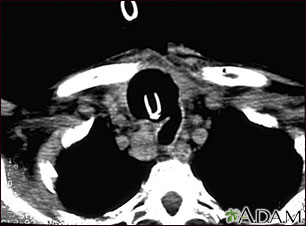

This CT scan of the upper chest (thorax) shows a malignant thyroid tumor (cancer). The dark area around the trachea (marked by the white U-shaped tip of the respiratory tube) is an area where normal tissue has been eroded and died (necrosis) as a result of tumor growth.